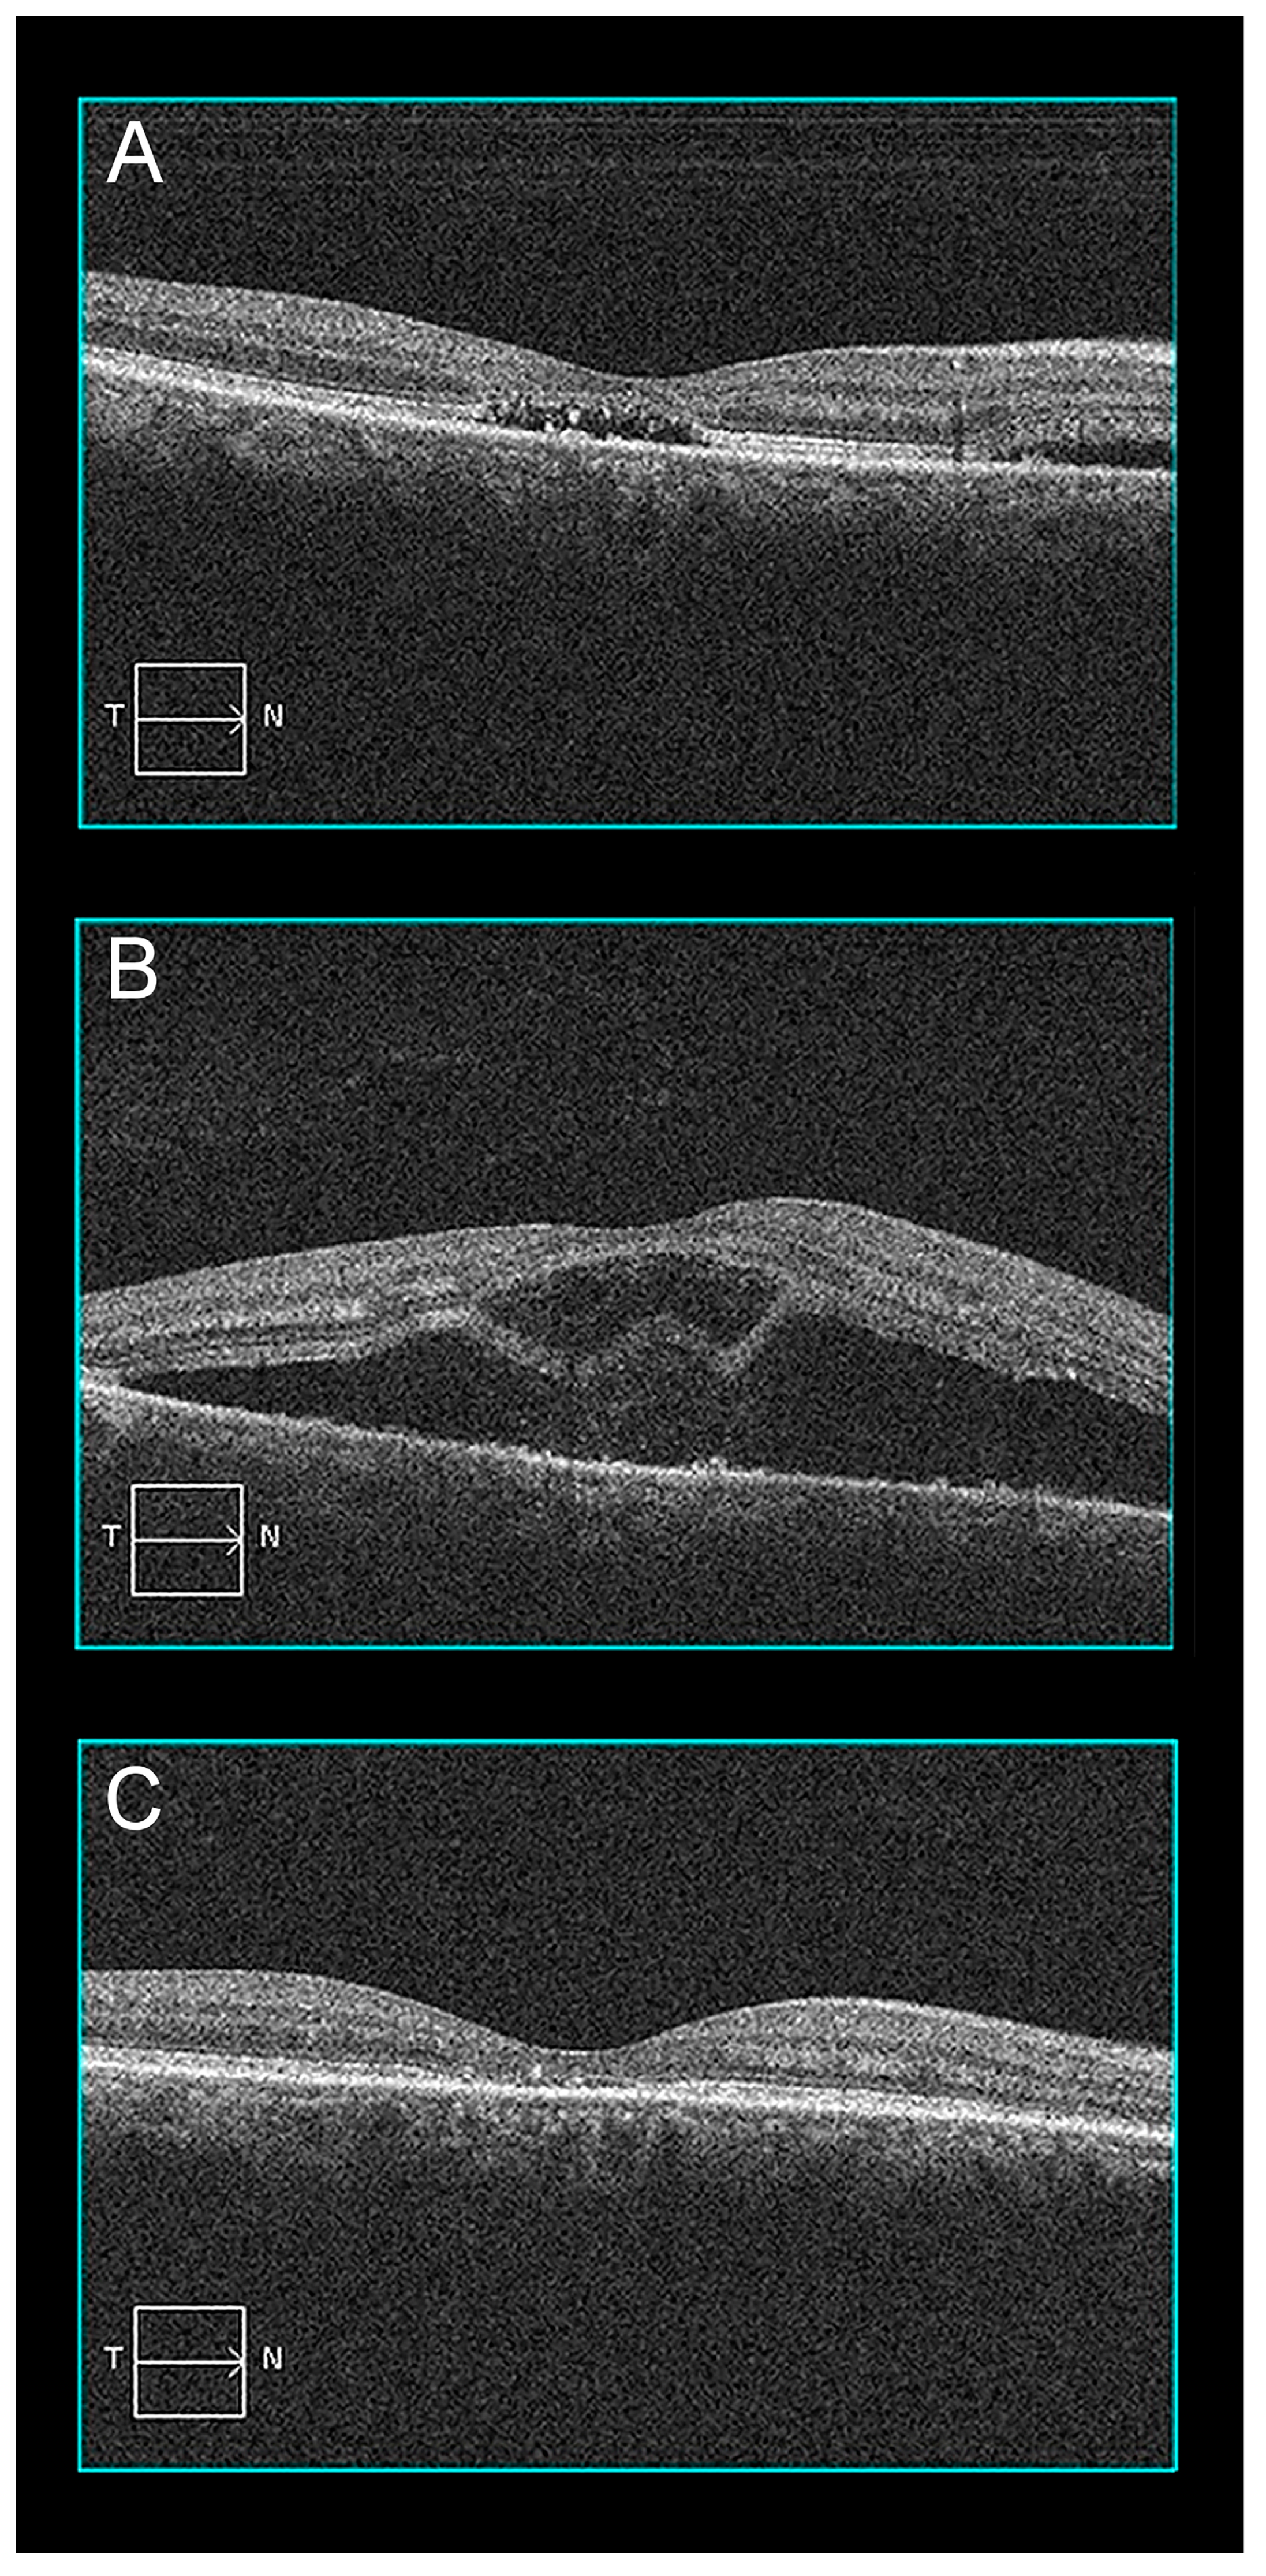

2.1. Case 1